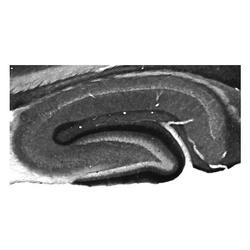

75-008 IHC

Full details

Method:

Other validation